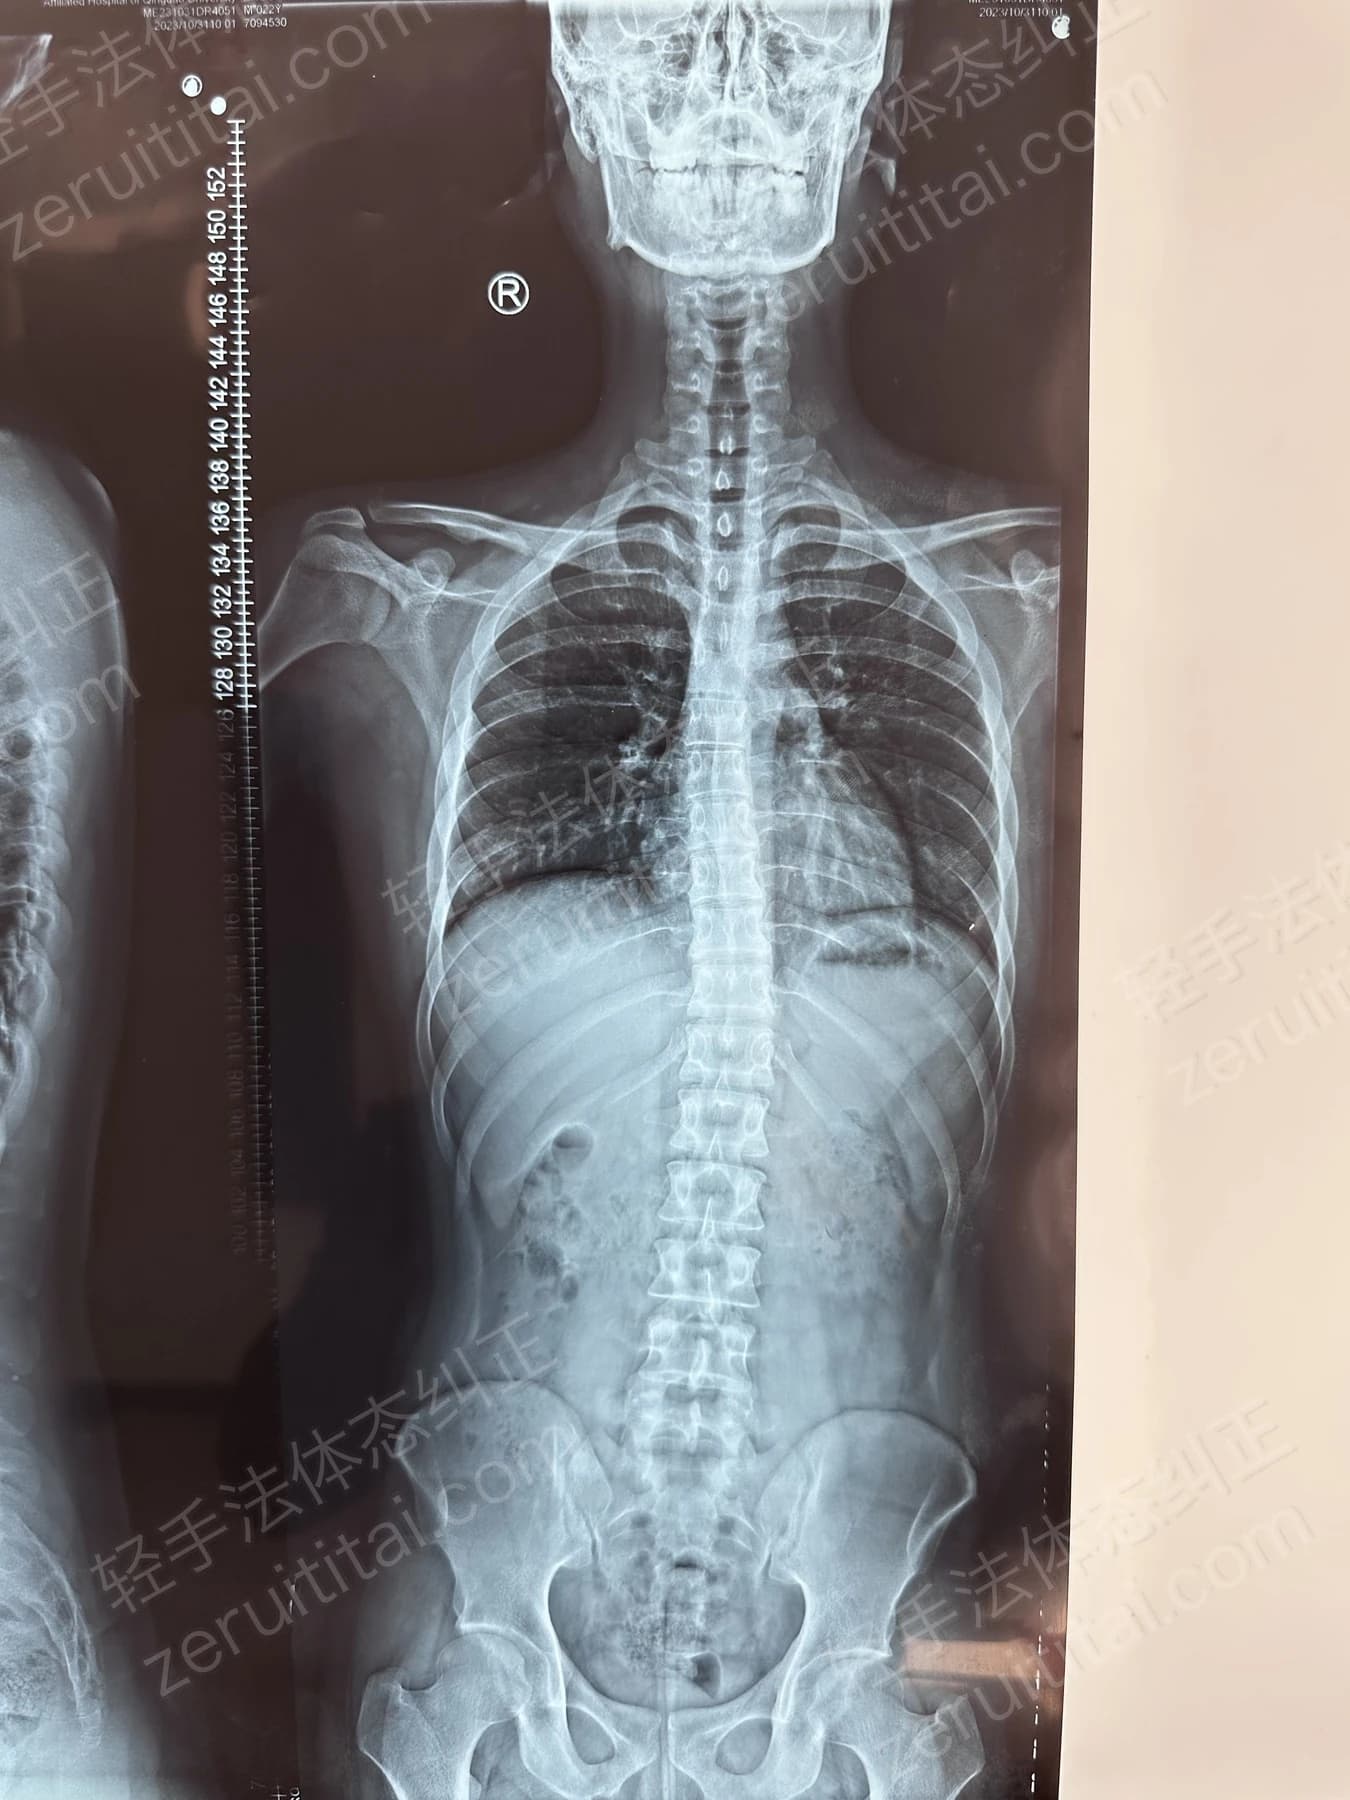

2023.05.30

第 4 次记录